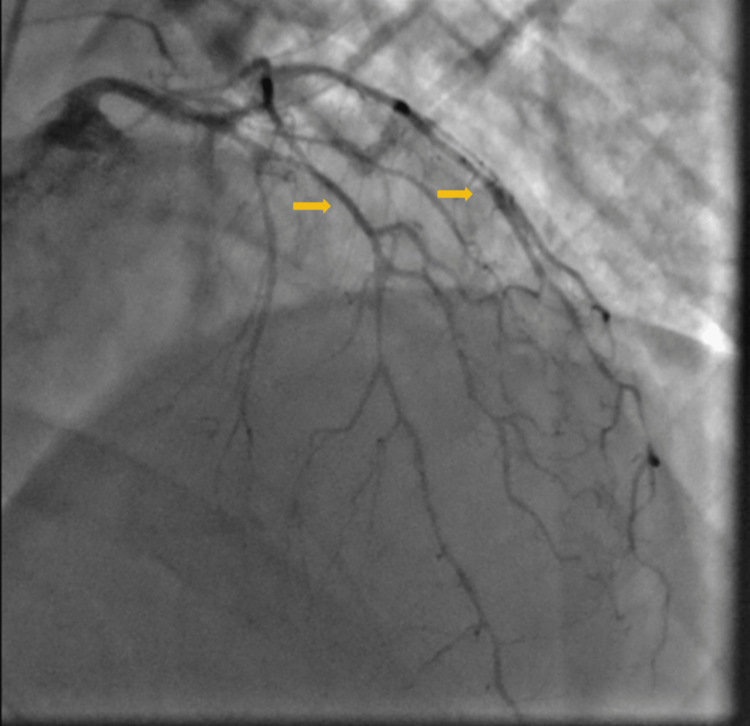

A 53-year-old male with a past medical history of hypertension, hyperlipidemia, and chronic obstructive pulmonary disease (COPD) presented with out-of-hospital cardiac arrest. The patient woke up with severe shortness of breath unresponsive to albuterol inhalers. Two hours later, the patient reported severe chest pain and was found pulseless. Emergency medical services (EMS) arrived and the patient was found to be in ventricular fibrillation. Cardiopulmonary resuscitation (CPR) was initiated, and the patient was intubated. The patient was shocked a total of five times, with four rounds of epinephrine and one round of amiodarone. Return of spontaneous circulation was achieved after 30 minutes. At the hospital, the patient’s blood pressure was 136/95 mmHg with no pressor support. Labs were significant for creatinine 1.5 mg/dl, bicarbonate 13 mmol/L, and lactic acidosis with pH 7.04. Troponins and brain natriuretic peptide(BNP) were within the normal range. EKG showed no dynamic ST segment changes on admission. UDS was positive for marijuana. The patient was urgently taken to the cath lab due to his presenting complaint of chest pain and ventricular fibrillation. Left Heart cath showed severe spasms involving all three coronary vessels responsive to intra-coronary nitroglycerin, but otherwise no significant obstructive coronary disease (Figures 1,2). He was started on a nitroglycerine drip for vasospasm.